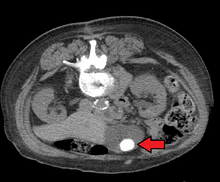

Images of a CT of gallstones

Mixed ("Brown Pigment") stones typically contain 20–80% cholesterol (or 30–70%, according to the Japanese- classification system).[30] Other common constituents are calcium carbonate, palmitate phosphate, bilirubin and other bile pigments (calcium bilirubinate, calcium palmitate and calcium stearate). Because of their calcium content, they are often radiographically visible. They typically arise secondary to infection of the biliary tract which results in the release of β-glucuronidase (by injured hepatocytes and bacteria) which hydrolyzes bilirubin glucuronides and increases the amount of unconjugated bilirubin in bile. Between 4% and 20% of stones are mixed.[3]